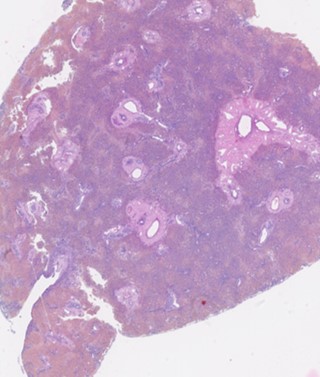

| Brittany Hodgkiss | Resident | Comparative Oncology | bhodgkiss@lsu.edu |

| Carlos Mendez Valenzuela | Resident | Radiation Oncology | cmendez@lsu.edu |